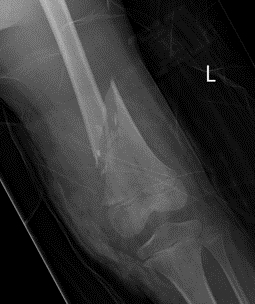

Distal Femoral Fracture SH2 APDistal Femoral Fracture SH2 Lateral

Salter Harris Type II